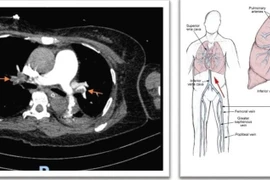

Hành trình cứu sống người bệnh ngừng tim do huyết khối gây bít tắc hoàn toàn 2 bên động mạch phổi được thực hiện khẩn trương, giúp bệnh nhân thoát cửa tử.